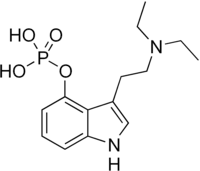

| Psilocybin | Fungi | 4-OPO3H2 | CH3 | CH3 | 4-phosphoryloxy-N,N-dimethyltryptamine | 520-52-5 |